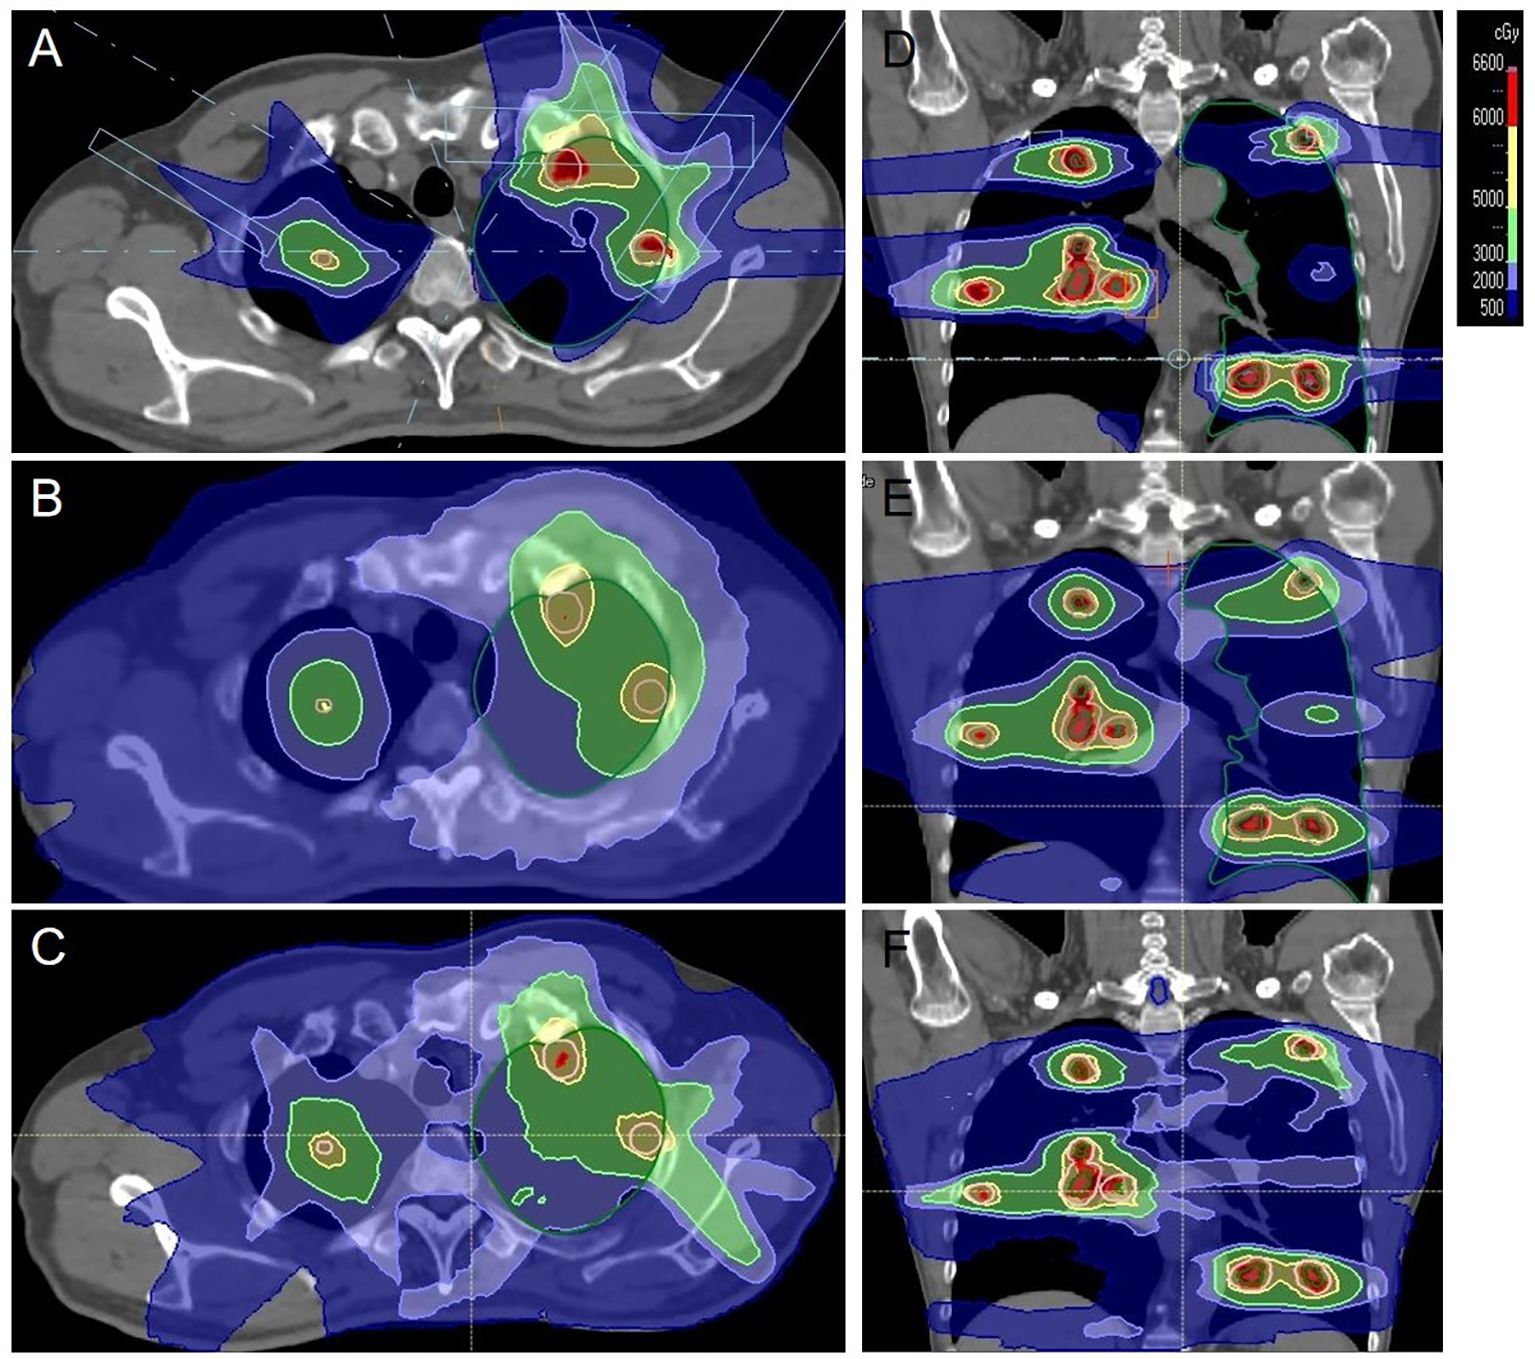

Adenoid Cystic Carcinoma (ACC) is characterized by its aggressive nature, high propensity for perineural invasion, and significant risk of distant metastasis, particularly to the lungs. Therapeutic options for locally advanced or metastatic ACC are limited, and conventional radiotherapy is often constrained by dose limitations for multifocal disease, leading to inadequate treatment. A 54-year-old male ACC patient, who had recurred after three prior surgeries, presented with PET/CT-confirmed bilateral cervical lymph node and multiple bilateral pulmonary metastases. Given the multifocal metastases and the critical need for sparing organs at risk (lungs, heart, esophagus), which rendered photon radiotherapy unable to meet the required dose constraints, proton therapy was employed with the following dose prescriptions: for pulmonary metastases: CTV 50 Gy(RBE) in 15 fractions, GTV 60 Gy(RBE) in 15 fractions; for the cervical lesion: GTVnd 70 Gy(RBE) in 28 fractions, CTVnd 66 Gy(RBE) in 28 fractions, CTV 50.4 Gy(RBE) in 28 fractions. Follow-up PET/CT post-treatment demonstrated complete resolution of some bilateral pulmonary metastases, with marked reduction in size and decreased metabolism in the remaining nodules. The metastatic cervical lymph nodes also showed reduced volume and metabolic activity. No adverse events exceeding Grade 2 occurred during the treatment course. This case demonstrates that proton therapy is highly suitable for multifocal ACC metastases, especially multiple small pulmonary nodules. Through its precise dose delivery, it enables high-dose irradiation (GTV 60–70 Gy(RBE)) to targets while significantly sparing normal organs. This approach represents a viable strategy for complex cases where conventional radiotherapy is contraindicated. It aims to delay disease progression and achieve organ preservation in refractory ACC.